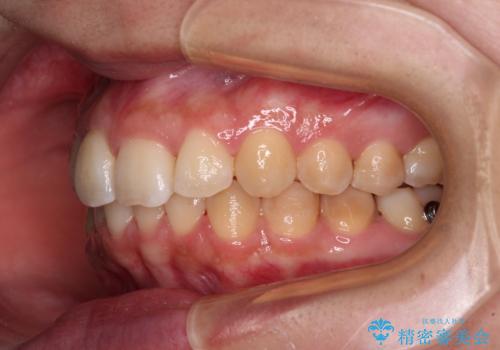

前歯のデコボコをインビザライン矯正で綺麗に改善

- 上下前歯のデコボコを気にして来院された患者様です。

全体的に叢生は軽度であったため、インビザラインにて矯正治療を行うこととしました。

舌の突出癖改善がうまくいかず、途中で舌小帯の切除を行いました。

気になる段差を納得いくまで改善させたため、治療期間は長くなりましたが、綺麗な仕上がりとなりました。